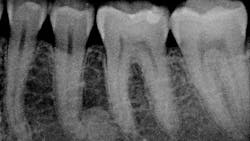

Patient: 27-year-old male

- Chief complaint: upper right tooth, third from the back, was bothering the patient progressively over the last few months

- Patient has slightly elevated blood pressure and is a chronic tobacco user

- Rough, corrugated-cardboard-like tissue in large area of lower left vestibule

- Patient is aware of the risks associated with tobacco